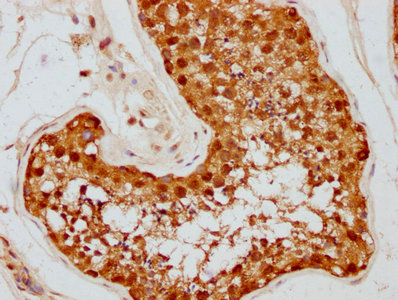

IHC image of CSB-RA011087A1HU diluted at 1:87.5 and staining in paraffin-embedded human testis tissue performed on a Leica BondTM system. After dewaxing and hydration, antigen retrieval was mediated by high pressure in a citrate buffer (pH 6.0). Section was blocked with 10% normal goat serum 30min at RT. Then primary antibody (1% BSA) was incubated at 4℃ overnight. The primary is detected by a biotinylated secondary antibody and visualized using an HRP conjugated SP system.